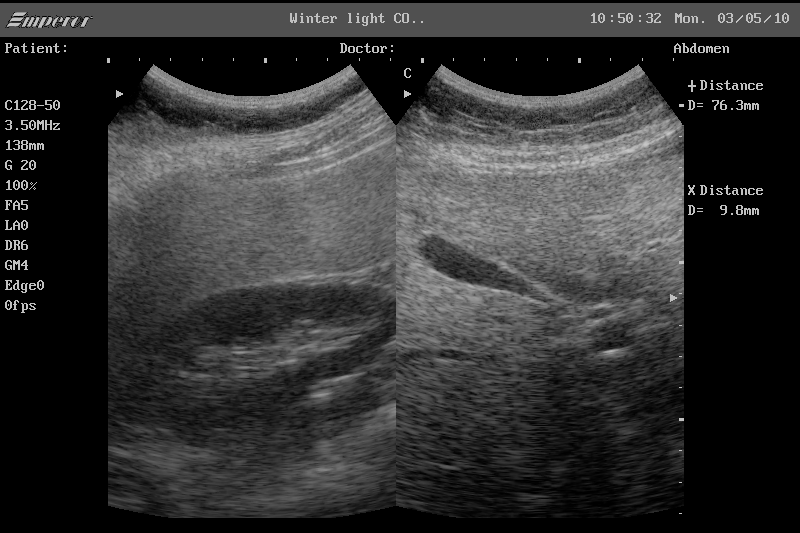

복부 초음파는 초음파(ultrasound)를 이용해 복부 내 장기들의 상태를 확인하는 비침습적 검사 방법입니다. 방사선을 사용하지 않아 인체에 해롭지 않고, 고통 없이 실시간으로 복부 장기들을 관찰할 수 있다는 점에서 가장 기본적이면서도 효과적인 진단도구로 평가받습니다.

초음파 탐촉자(Probe)에서 발생한 고주파 음파가 인체 내부 장기에 부딪혀 반사되며, 복부 초음파로 알 수 있는 것은 바로 이 반사파를 영상화해 간, 담낭, 췌장, 비장, 신장(콩팥), 방광, 대동맥, 림프절 등의 상태를 분석하게 됩니다.